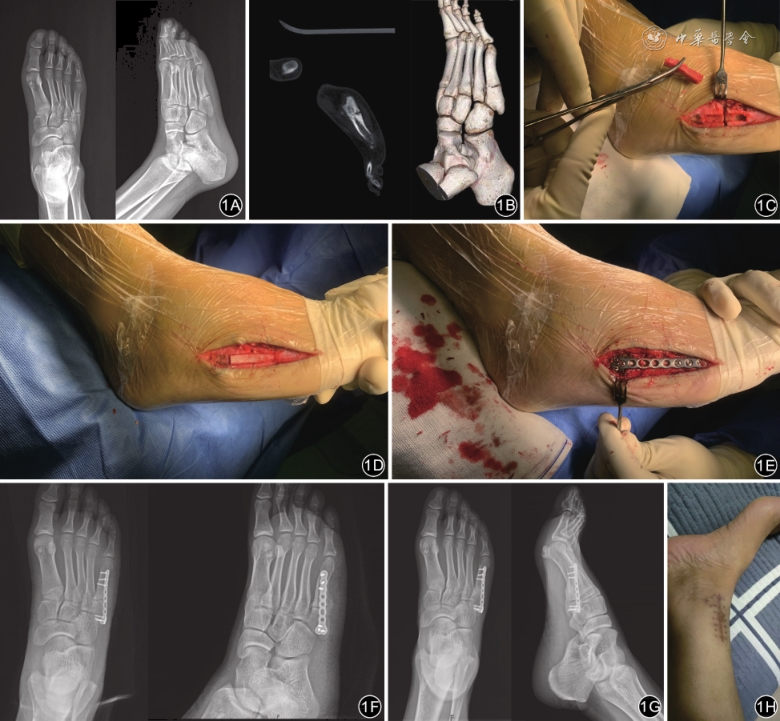

患者手术均由同一位高年资创伤骨科医生主刀、同一组创伤团队完成。患者取仰卧位,硬膜外麻醉。消毒前在C臂X线机透视下确认骨折线位置并做标记。于足背外侧以骨折线为中心做平行于第五跖骨长约6 cm的纵切口,分离软组织,注意保护血管及腓肠神经外侧分支,逐层切开直至显露骨折端。用薄骨刀清理断端两侧硬化骨、纤维瘢痕组织,直至新鲜骨质显露。以骨折端为中心,凿除两侧跖骨背侧骨质,各长约1.5 cm、宽约5 mm,形成一长方形的空槽。在同侧肢体内踝上方做长约4 cm纵切口,分离并显露胫骨远端内侧骨质,用骨刀凿取一长约3.0 cm、宽约0.5 cm的长方形骨块,将其适当修剪后放置于第五跖骨骨折端骨槽内并压实。最后于长方形骨块上方跨越骨折端放置1枚2.4 mm系统钢板(美国豪迈公司产品),并用锁钉固定。术中透视见骨折端复位良好,植骨块位置好,钢板及螺钉位置满意,冲洗切口并逐层缝合。

患者手术均顺利。术后获随访12~25个月,平均18个月。根据影像学检查10例患者均骨折愈合,时间为6.0~10.0(7.2±1.0)周。术后6.0~7.0周(平均6.8周)骨折临床愈合9例,延期愈合1例(术后10.0周)。无再骨折,参加正常训练时间7.0~11.0(9.8±1.0)周。术后并发症的情况:10例患者中均无切口感染;2例出现腓肠神经炎的患者,术后通过营养神经药物治疗3周后逐渐好转;取骨部位均无术后切口感染、皮肤感觉异常等。见表1。典型病例见图1。